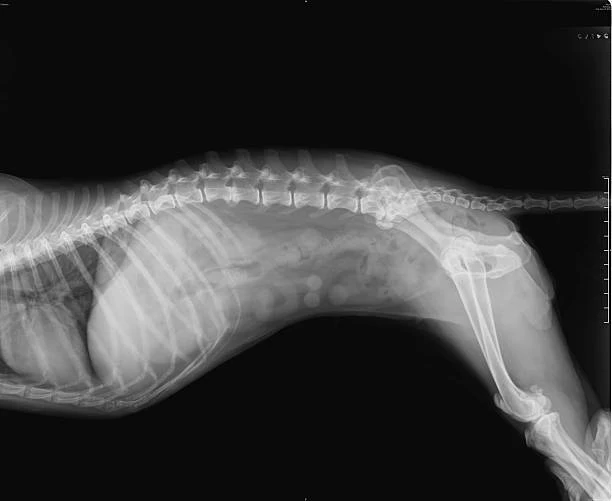

Exames de Imagem e Raio-X

Um dos principais diferenciais da clínica é a disponibilidade de exames de imagem, como o raio-x, que facilitam o diagnóstico preciso e o acompanhamento de tratamentos.

Com um aparelho de raio-x moderno e equipe especializada, a RaçãoPet Saúde Animal garante agilidade na identificação de possíveis problemas de saúde e na definição do melhor plano terapêutico para cada animal.